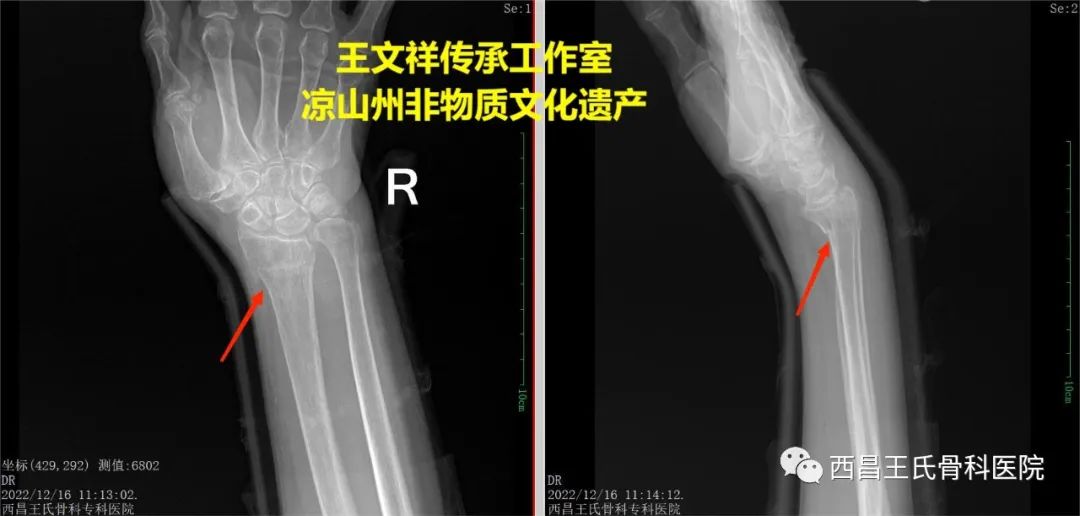

手法复位病例七:尺桡骨骨折

图片

复位前

复位后